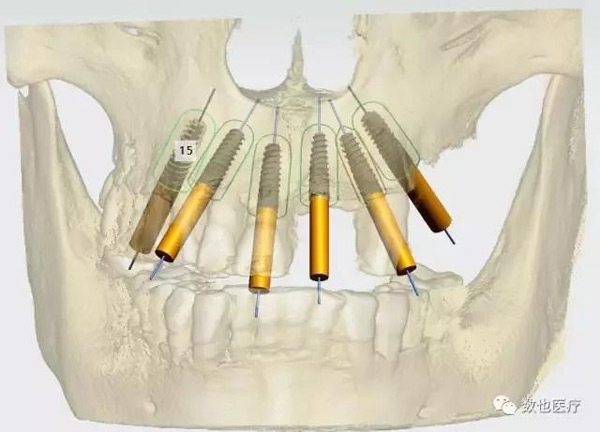

患者上颌骨条件较差,拔牙后存在较多的拔牙窝。考虑做即刻修复需要较好的初期稳定性,根据患者颌骨情况,计划种植6颗cortex种植体,避开骨缺损区域,远中两颗倾斜避开上颌窦。

设计完成种植导板